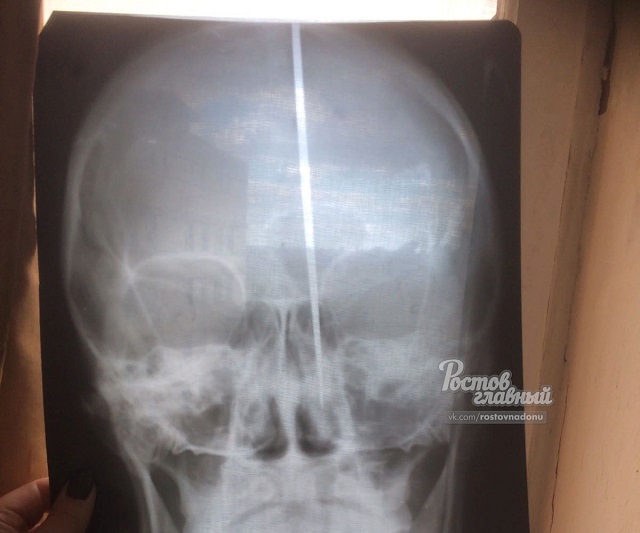

Жителю Донецка Юрию, который накануне прославился на всю страну тем, что воткнул себе в голову нож и остался в общем и целом невредим, успешно провели операцию. По информации «КП-Ростов-на-Дону», над Юрой поработали нейрохирурги из Ростова, так как донецкие медики не решились браться за столь сложный случай и обратились к коллегам из донской столицы.

Выяснилось, что мужчине попросту повезло — лезвие ножа вошло в голову хоть и практически целиком, но попало чётко между двумя полушариями мозга.